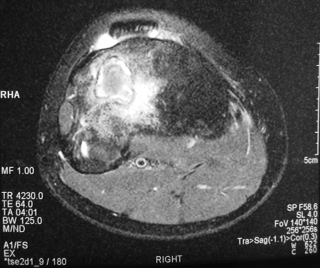

Fig. 4

Fig. 5

Fig. 6

Fig. 7

Fig. 4-7: MR imaging of a benign fibrous histiocytoma of the proximal tibia demonstrates a heterogeneous high signal intensity and low signal intensity with surrounding sclerotic bone on T2-weighted images. T1-weighted images show low signal intensity. No soft tissue mass is visible.